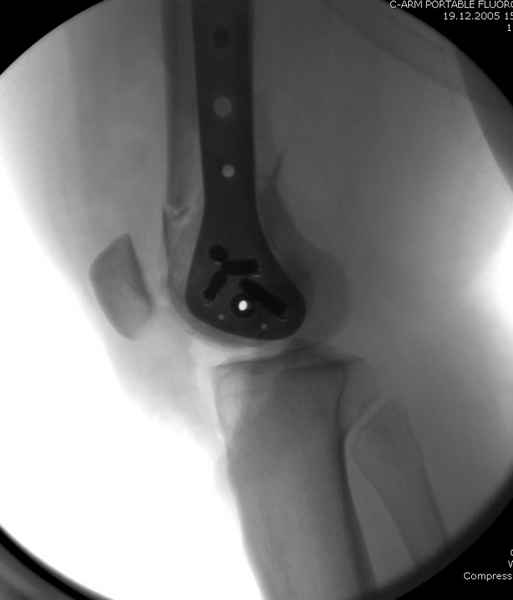

Уважаемые коллеги! От имени Алексея Смирнова всем спасибо за обсуждение. Больной прооперирован. Снимки в приложении.

При наличии различных имплантов, любые варианты: слева (полу) открытым - мининвазивным, а справа закрытым интрамедуллярным методом, его считаем более чем приемлемым для фиксации данных переломов.

Проксимальная и дистальная блокировка, независимо от техники введения штифта, ретроградно или антеградно, гарантирует сращение сегментарных переломов бедра без укорочения. Штифты диаметром 12 мм с блокировкой сверху и вниз двумя шурупами выдерживают вес 75 кг больного, что позволяет раннюю профилактику контрактур.